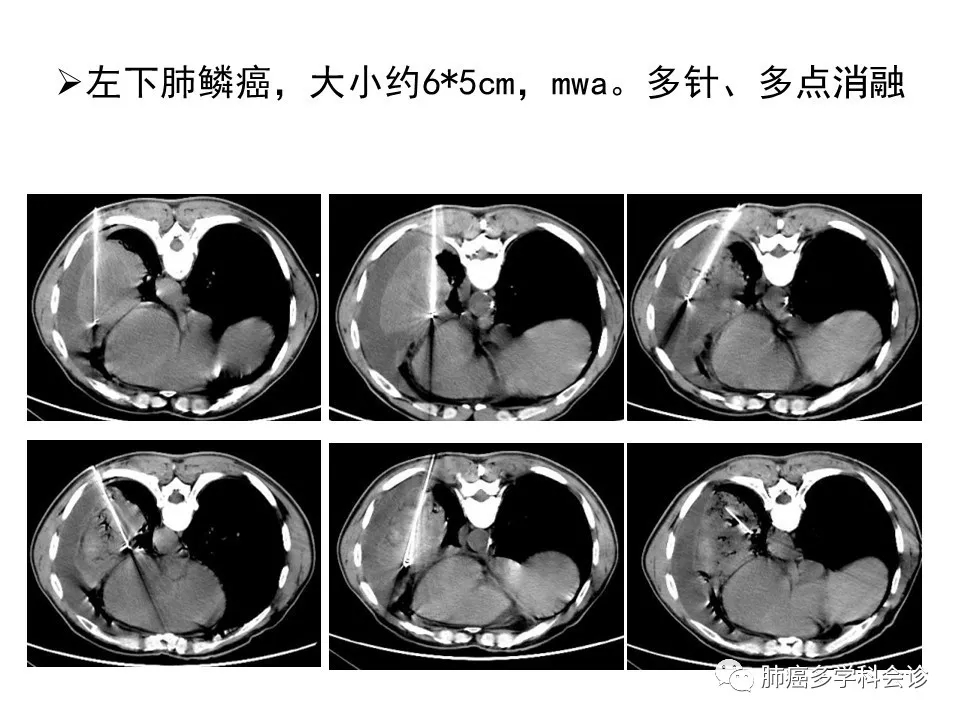

肺癌微创治疗时机的选择